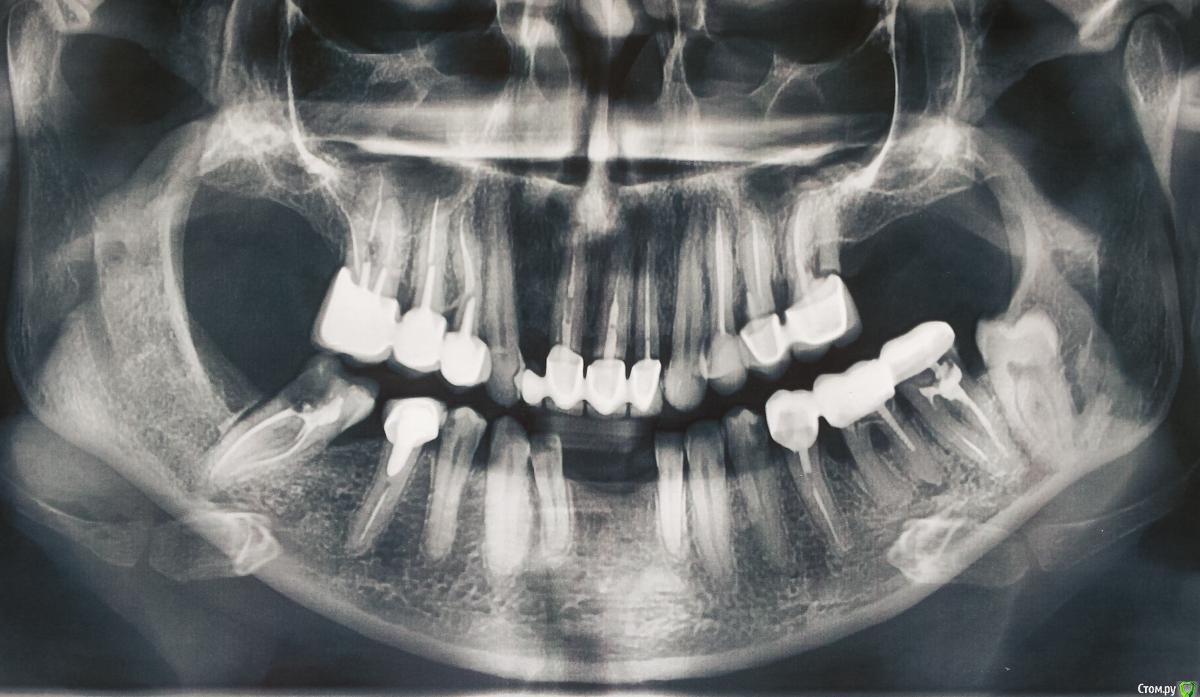

Мар Опубликовано 24 мая, 2020 Поделиться Опубликовано 24 мая, 2020 Мне 48, хотелось что-то еще сохранить при пожизненном лечении и протезировании. Вопрос о нижней челюсти. Возможно ли сохранить клыки. Предлагают сделать всю нижнюю челюсть сразу. Сейчас на передние зубы съемный протез. Если его оставить, можно ли протезировать боковые зубы по отдельности?Готова к такому дискомфорту только ради сохранения клыков. Ссылка на комментарий

Мар Опубликовано 29 мая, 2020 Автор Поделиться Опубликовано 29 мая, 2020 Протезист сказал, если удастся поставить штифт в правый последний зуб (вообще он у них идет на удаление..) тогда можно протезировать, захватив удаленные передние и левую сторону, иначе правая сторона не выдержит нагрузки. естественно обтачиваются клыки. Ссылка на комментарий

chervoncevdaniil Опубликовано 29 мая, 2020 Поделиться Опубликовано 29 мая, 2020 (изменено) Если вы планируете замещать передние отсутсувующие зубы мостовидным протезом,то в вашем случае опора на клыки тоже желательна,вторые зубы не самый лучший вариант для опоры мостовидного протеза в долгосрочной перспективе Изменено 29 мая, 2020 пользователем chervoncevdaniil Ссылка на комментарий

Мар Опубликовано 29 мая, 2020 Автор Поделиться Опубликовано 29 мая, 2020 Если вы планируете замещать передние отсутсувующие зубы мостовидным протезом,то в вашем случае опора на клыки тоже желательна,вторые зубы не самый лучший вариант для опоры мостовидного протеза в долгосрочной перспективеВы правильно меня поняли. Первоначально я так и планировала. А сейчас думаю, может протезировать только три зуба, если это возможно. А на передние в перспективе либо сделать навесной протез отдельно, либо поставить импланты (опять же, если это возможно).Еще при обтачивании клыков придется удалять нерв или оставить зуб живой? Ссылка на комментарий

Мар Опубликовано 2 июня, 2020 Автор Поделиться Опубликовано 2 июня, 2020 "Это оптимальный вариант,клыки препарировать под коронки нужно только в случае,когда других альтернатив не остаетсяСпасибо, вы мне помогли. Сегодня правый последний зуб стоматолог приготовила под вкладку. Протезист закроет под коронки правые крайние два зуба. Правда гарантий никто не дает, сколько простоят..., но зато свои! А передние удаленные может быть заменю имплантами, пока только настраиваюсь... Имлантолог сказал, что надо удалять двойки и в лунки ставить имплант.. Я пока не готова к этому. Ссылка на комментарий